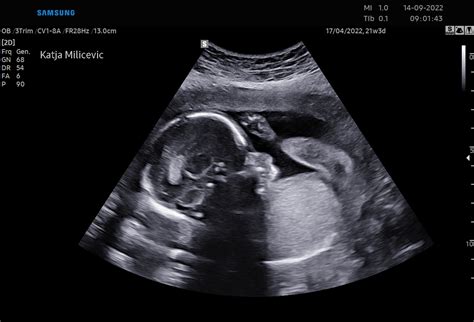

Otrokov obraz je oblikovan skoraj v celoti. Otrok zdaj že lahko voha, sliši in okusi, razvoj njegovih senzoričnih celic na različnih delih telesa pa pomeni, da je občutljiv na okolico in počasi že zaznava stvari. Zaradi povečanega zaznavanja in zavedanja se lahko ustraši glasnih zvokov - če boste v tem času imeli ultrazvočni pregled, boste lahko videli, kako njegovo telesce trzne. V 17. tednu nosečnosti lahko otrok že zaznava tudi svetlobo in temo, na primer, ko sonce sije na vaš trebuh.

3D/4D ULTRAZVOK NUHALNA SVETLINA - DEJANSKI PRIKAZ PLODA V MATERNICI (BARVE)